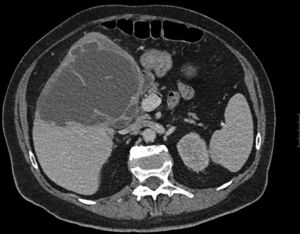

Mujer de 70 años hipertensa, diabética y con cardiopatía hipertensiva, que consulta por dolor en hipocondrio derecho de 2 semanas de evolución, fiebre y vómitos. Presenta fracaso renal e hipotensión refractaria. La TC urgente evidencia una colecistitis aguda litiásica con un absceso hepático de 13cm. Se realiza drenaje percutáneo urgente ecoguiado en quirófano, iniciando antibioterapia y soporte hemodinámico. Tras buena evolución clínica, es dada de alta al décimo día (figs. 1 y 2).